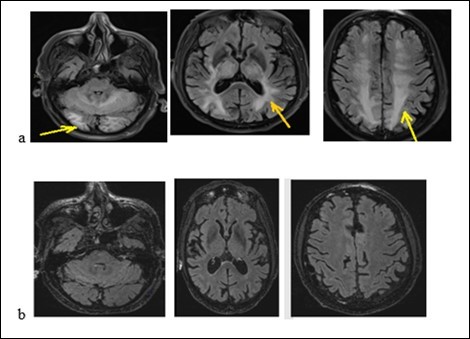

A 31-year-old pregnant woman was admitted to hospital because of headaches, vomiting and rotational dizziness on December 29, 2017. A series of headache followed by vomiting and dizziness began at 33 weeks of pregnancy (a month before her admission). We noticed that the blood pressure reached 150 / 90mmHg. She was treated with oral nicardipine for one month. The delivery took place without postpartum complications. She had been treated with bromocriptine for breast congestion. Three days after delivery, she had thunderclap posterior headache, nausea chills with asthenia without fever, polyuria and polydipsia. The manifestation of the headache was 9.5 / 10 on the Visual analogical Scale. In her medical history, she underwent a surgery of an ovarian cyst and a left temporal arachnoid cyst in 2007. She is an active smoker at 15 boxes-years. The neurological and other physical examinations were normal. The routine biological, metabolic, infectious and immunological check-up was normal. The MRI had displayed a subarachnoid hemorrhage associated with hypersignals on Flair sequences of bilateral hemispherical cortex, on the central gray nuclei and the cerebellar hemispheres. The Angiography had not shown any stenosis. The MRI (Figure 3) had displayed on diffusion sequences, two punctiform infarction of right putamen and caudate nuclei. The apparent diffusion coefficient was high for the other bi-frontal lesions. All these findings led us to conlude with RPE syndrome complicated by subarachnoid hemorrhage and cerebral ischemia. The patient had been treated with decreasing dose of nimodipine for three months. At 6 weeks of progress, the neurological examination was normal. The Brain MRI (Figure 3b) displayed a complete decrease of the flair hyper signals from the basal ganglia and the cortex. The outcome was good.

Figure 3.The brain MRI with flair sequences showing bi-temporal and frontal hyper signals (a) and a complete decrease of lesions after treatment (b).

An old man of 74 called J. R. was admitted to hospital on January 26, 2018 for generalized tonic-clonic seizures. The symptoms began 2 weeks before his admission by abdominal pain, vomiting, diarrhea without fever. They were followed by generalized tonic-clonic seizures. According to his medical history, he suffers from high blood pressure, non-insulin-dependent diabetes, chronic obstructive pulmonary disease (COPD), moderate renal failure on a single kidney. He underwent a left nephrectomy for a papillary urothelial tumor, a right upper pulmonary lobectomy for the removal of a bronchial adenocarcinoma. He has been treated with Gemcitabine (Gemzar) and by Fluorine uracil (Folfox) for a pancreatic adenocarcinoma. He also has 3 adrenal nodules. The physical examination noted drowsiness but the patient was reactive to minor stimuli with a Glasgow score of 13/15, a flaccid right hemiplegia. We noted that there was not a neck thifness. Besides, the blood pressure was 210/95 mm Hg and the heart rhythm was regular without heart murmur or additional noises. The rest of the physical examination was normal. The biological check-up had shown a creatinine level at 203 micromol/l with a clearance at 29.9 ml/min, a hyperkalaemia at 6 mmol/l and a hypercalcemia at 2.62 mmol/l. The CSF study had shown a hyperproteinorachy at 0.940g / l, a glycorachy at 5.6 g/l, the CSF count cell displayed 6 cells/mm3 without germ. The brain MRI (Figure 4a) had displayed on flair sequences, diffuse and symmetrical hyper signals of the sub-cortical white matter of the temporal, occipital, frontal lobe and the cerebellum. These radiological findings evoked a RPE syndrome. The treatment included hyperhydration and an anti-epileptic drug. The outcome was noticeable with the decrease of symptoms. We relied on the diagnosis of RPE syndrome. The brain MRI checking-up (Figure 4b) at 40 days was displaying a complete decrease of the lesions.

Figure 4.Brain MRI with flair sequences showing hyper signals of white matter and cerebellum corresponding to edema (a) and the decrease of lesions after treatment (b).